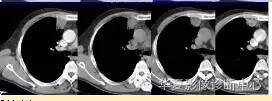

周围GGO边界清楚,分叶征、胸膜凹陷征、含气支气管,混合型GGO

磨玻璃结节良恶性影像分析策略 混合型,边界清楚、分叶征,考虑肺癌

磨玻璃结节良恶性影像分析策略 磨玻璃结节良恶性影像分析策略磨玻璃结节良恶性影像分析策略 其中血管显示清楚,GGO

边界清楚,分叶征,空泡征